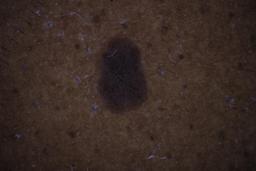

ISIC_6598546

Clinical

| Field | Value |

|---|---|

| age_approx | 60 |

| anatom_site_1 | Trunk |

| anatom_site_2 | Posterior trunk |

| concomitant_biopsy | False |

| dermoscopic_type | contact polarized |

| diagnosis_1 | Benign |

| diagnosis_confirm_type | single contributor clinical assessment |

| fitzpatrick_skin_type | VI |

| image_manipulation | instrument only |

| image_type | dermoscopic |

| lesion_id | IL_6711989 |

| patient_id | IP_8590441 |

| sex | male |